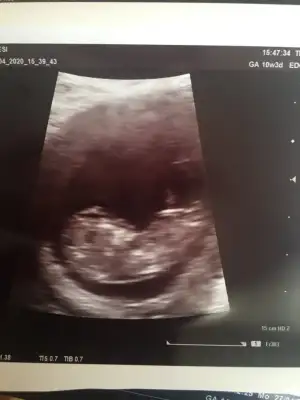

Erkek gibi nubu karanlık zor seçiliyor 13 haftayıda paylaşınİkra Meyra canım burada 11+6 haftalık olduk var mı bir tahmin nin

Kız yönünde12 olsa teyit ederim